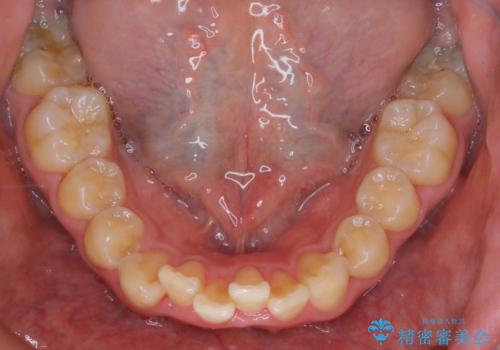

- 上顎前歯の突出感と下顎前歯のガタつきが主訴で来院されました。

出っ歯とガタつきの改善を行うには抜歯が必要と診断し、上下左右第一小臼歯を抜歯する計画を立てました。

抜歯する事で歯の移動量が大きいことからワイヤー表側矯正装置で治療を行うことになりました。